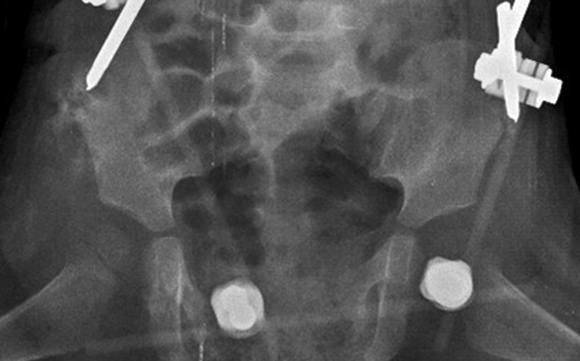

A los 13 días, la paciente presentó evolución satisfactoria y se consideró uso de tutor externo como dispositivo de manejo definitivo de la fractura durante mínimo 1 mes. Tuvo seguimiento ambulatorio. En radiografía de control se evidenció diástasis púbica de aproximadamente 10 cm (fig. 3); por tanto, al día siguiente se retiró el tutor externo, se efectuó el lavado y el desbridamiento de los tractos de clavos.